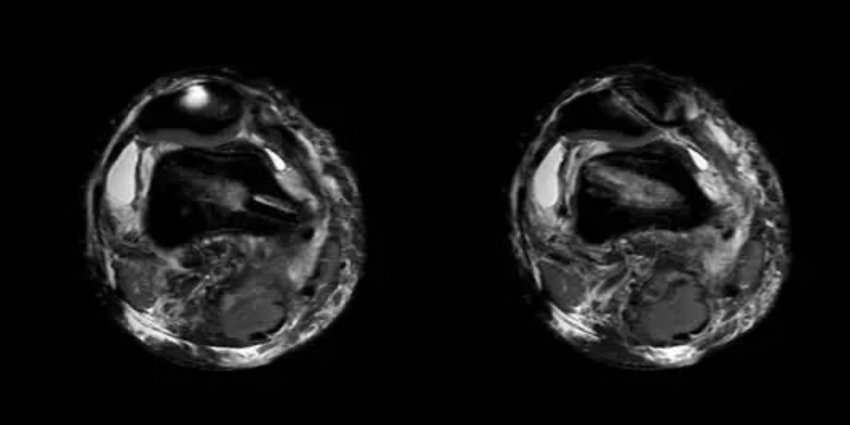

管床医师张鹏飞任耐心细致的讲解病情,患者同意行内侧副韧带重建术,术前却顾虑术后伤口留疤、康复困难等。经科主任徐明杰的耐心开导,患者最终下定决心行手术治疗。手术由徐明杰主任主刀,顺利完成了关节镜下内侧副韧带重建+半月板成形术(见图2、图3)。术后切口愈合良好,术后仅4天即出院。出院后,张鹏飞主治医师及时随访,并通过微信指导患者行康复锻炼,取得良好的效果(见图4)。

图3 术后复查MRI